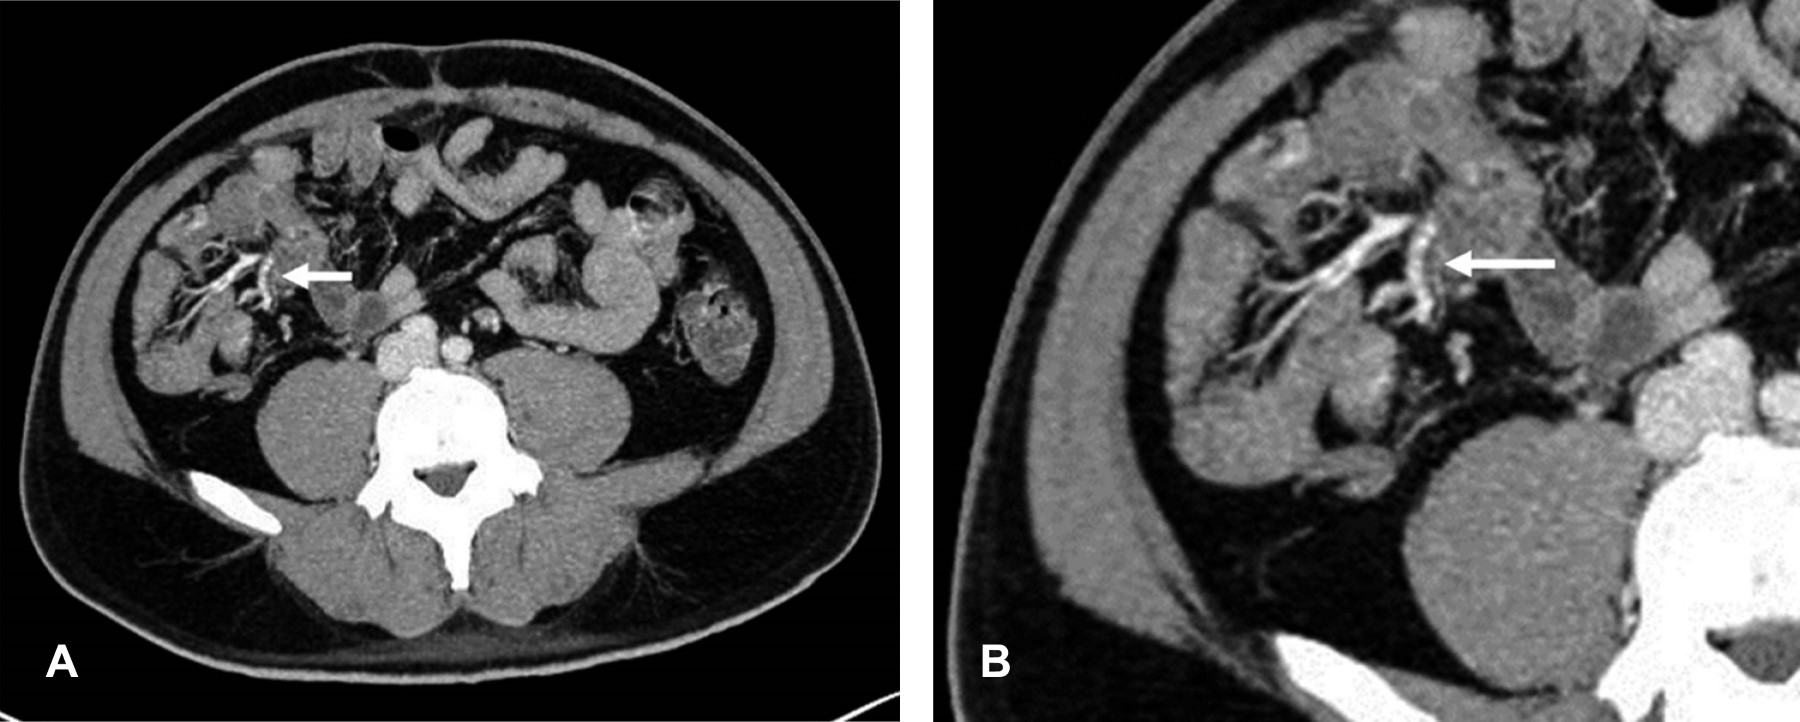

Introduction: polyarteritis nodosa (PAN) is a necrotizing vasculitis presenting as a multisystem disease. With aneurysmal formations in visceral arteries, especially in superior mesenteric artery branches. Case report: a 44-year-old male with abdominal pain in the epigastrium, nausea, and hematochezia, presenting petechiae on the trunk, abdomen, and pelvic limbs, predominantly with neutrophilic leukocytosis, negative immunological markers (ANCA). In abdominal angiotomography, sacculations are observed in superior ileal vessels. Conclusion: PAN is a rare multisystem vascular disease with a predilection for medium-caliber vessels. It is essential to identify radiological signs since a diagnostic delay leads to complications such as intestinal ischemia, aneurysmal ruptures, and others.

Figure 1